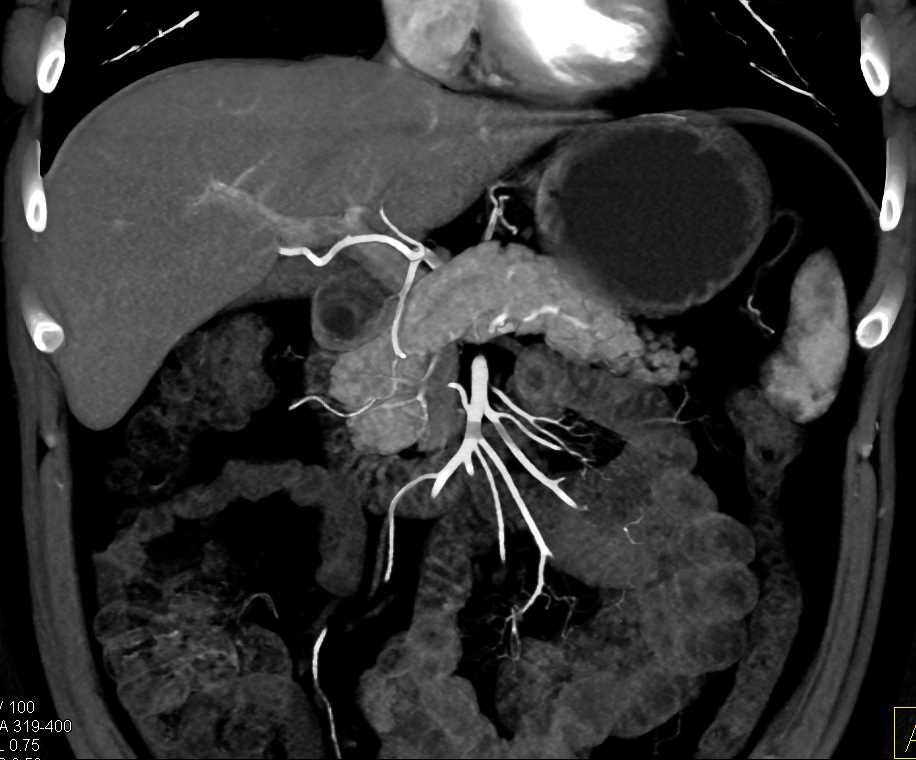

Neuroendocrine Tumor Body of Pancreas